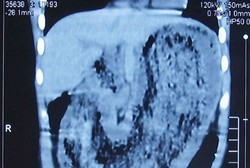

Bocah delapan tahun bernama Liuniu Liang mengalami kurang gizi karena ia tidak mau makan apa-apa. Anehnya, Liang tidak sakit sama sekali. Benar saja, setelah diperiksa, ternyata ada kumpulan rambut seberat 2 kg di perutnya.